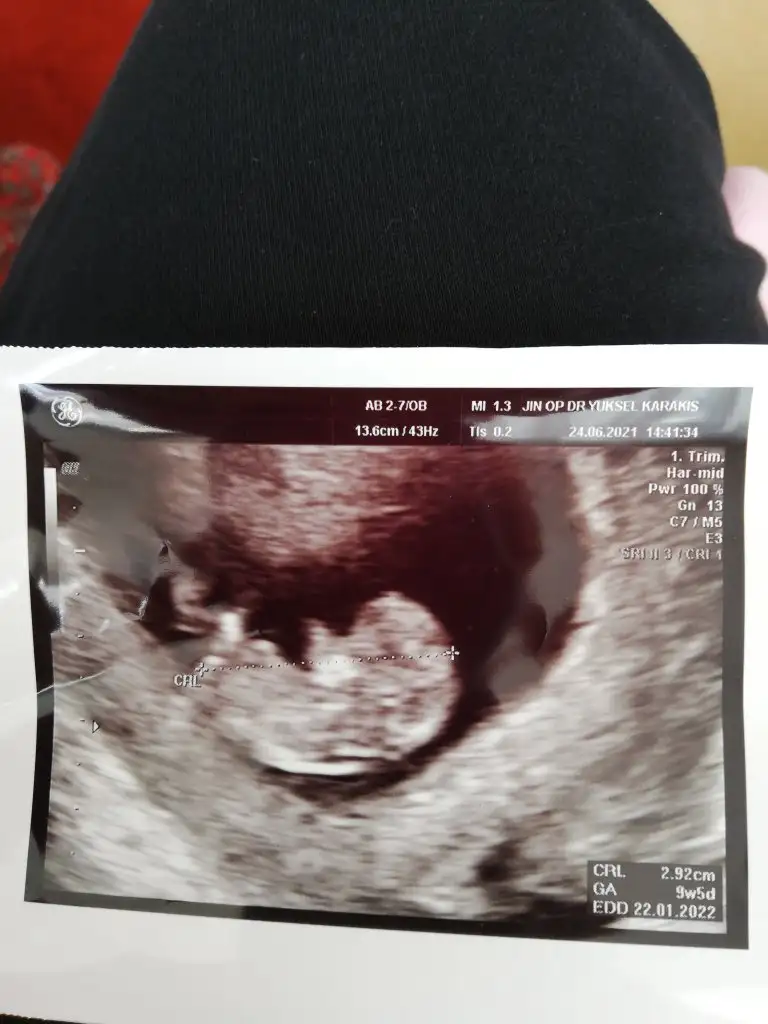

Kız diyorum benBende miniğimi gördüm geldim bugün şükürler olsun Bi sıkıntı yok 9+5günlük buda resmi kuzum cinsiyet tahminleri gelsin bakalım

Ben kız diyorum içimden öyle geldi hayırlısı olsun sagliklı hayırli evlat olsunBende miniğimi gördüm geldim bugün şükürler olsun Bi sıkıntı yok 9+5günlük buda resmi kuzum cinsiyet tahminleri gelsin bakalım